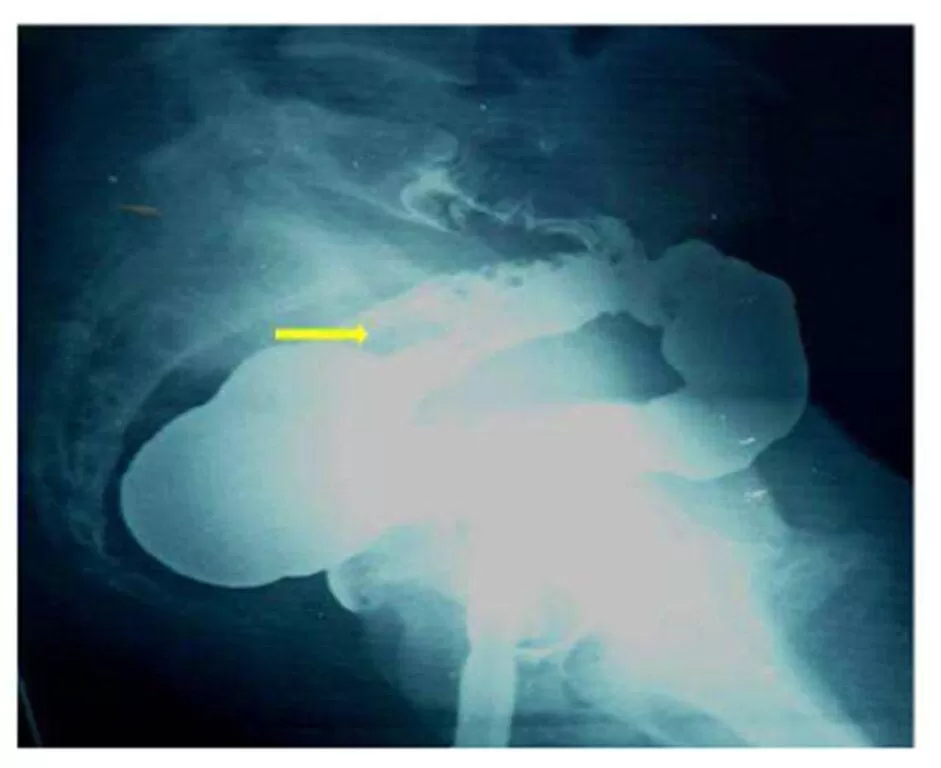

Barium enema (Fig.2 A & B) demonstrated luminal narrowing with irregularity of the wall of proximal sigmoid colon at the site suspected of presence of fistulous communication on HSG. Sagittal-T2 weighted MR image showed thinning of myometrium in the anterior wall with the presence of ill-defined fat plane and adjacent sigmoid loop attached to the anterior surface of the uterus (Fig.3). It indicated the site of the fistulous tract.

Figure 2: A (Oblique) & 2B (Lateral View):  Single contrast barium enema showing luminal narrowing with wall irregularity (arrows) of proximal sigmoid colon at site suspected of presence of fistulous communication during HSG.